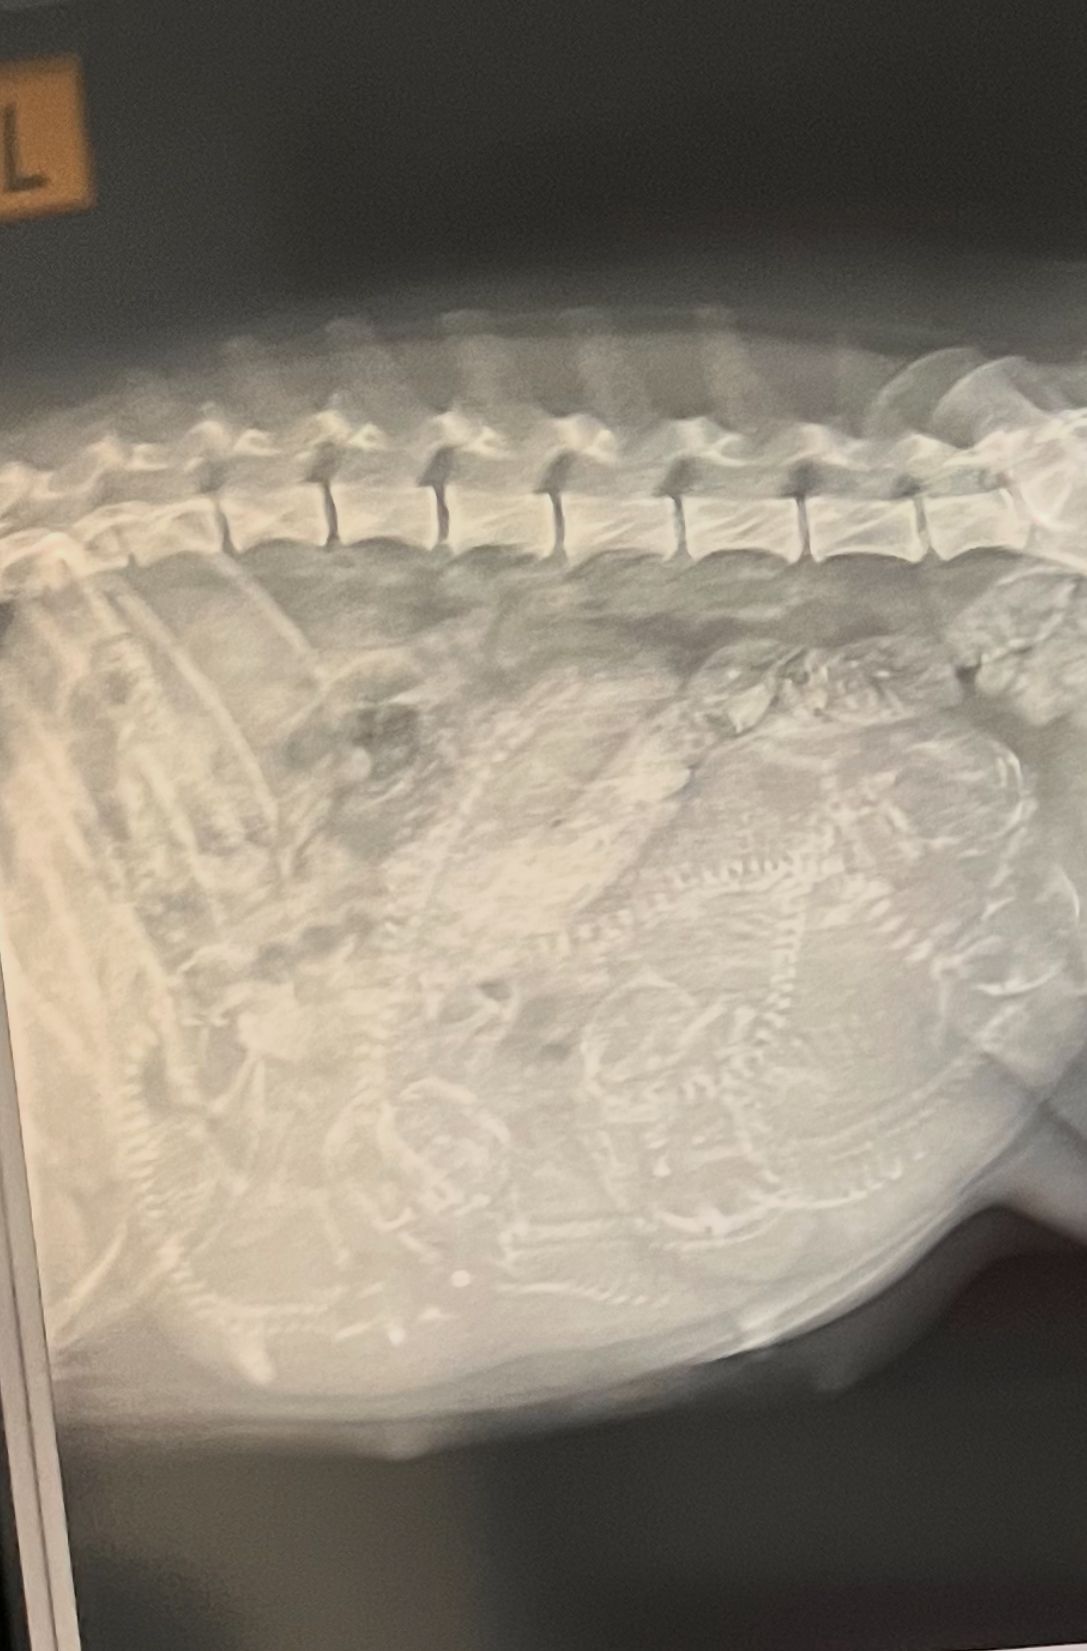

Heute war Röntgen angesagt, es bleibt bei sechs bis sieben, leider war der Darm von Fleur noch voll so das eventuell jemand dahinter verstecken könnte.